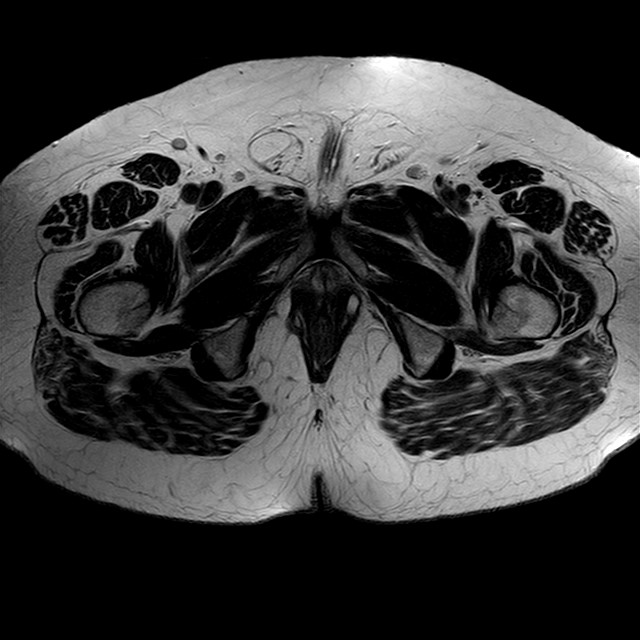

Esami: RMN BACINO

eT2w TSE

Evidenti e simmetriche alterazioni osteofitosiche in regione coxo femorale con riduzione delle rime articolari. Degenerazione completa del cercine glenoideo. Non attuali segni di versamento articolare. Non segni di edema osseo che escludono attuale algodistrofia od osteonecrosi. Lieve e simmetrica riduzione del trofismo della muscolatura glutea.